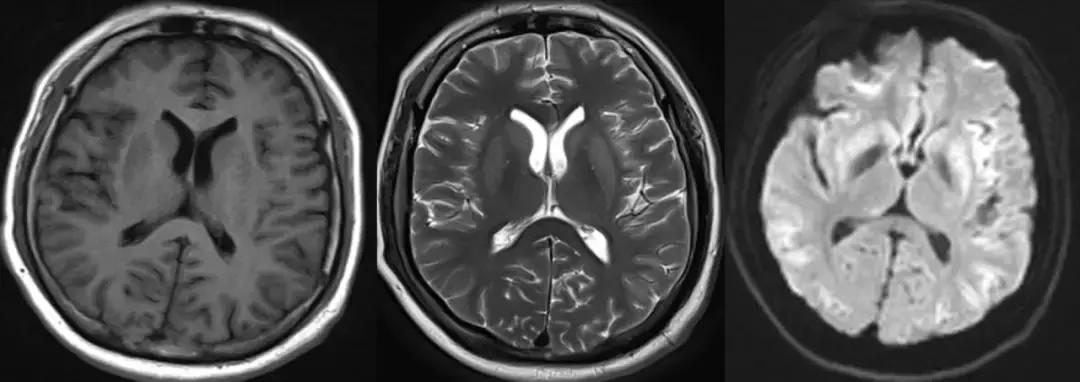

头颅 MR 检查结果如下图(由左-右),T1 像:双侧豆状核、壳核低信号,T2 像:双侧豆状核、壳核高信号,DWI 像: 双侧豆状核、壳核高信号。

目前诊断为:EPM,目前患者病情未进一步加重,正在随访中。